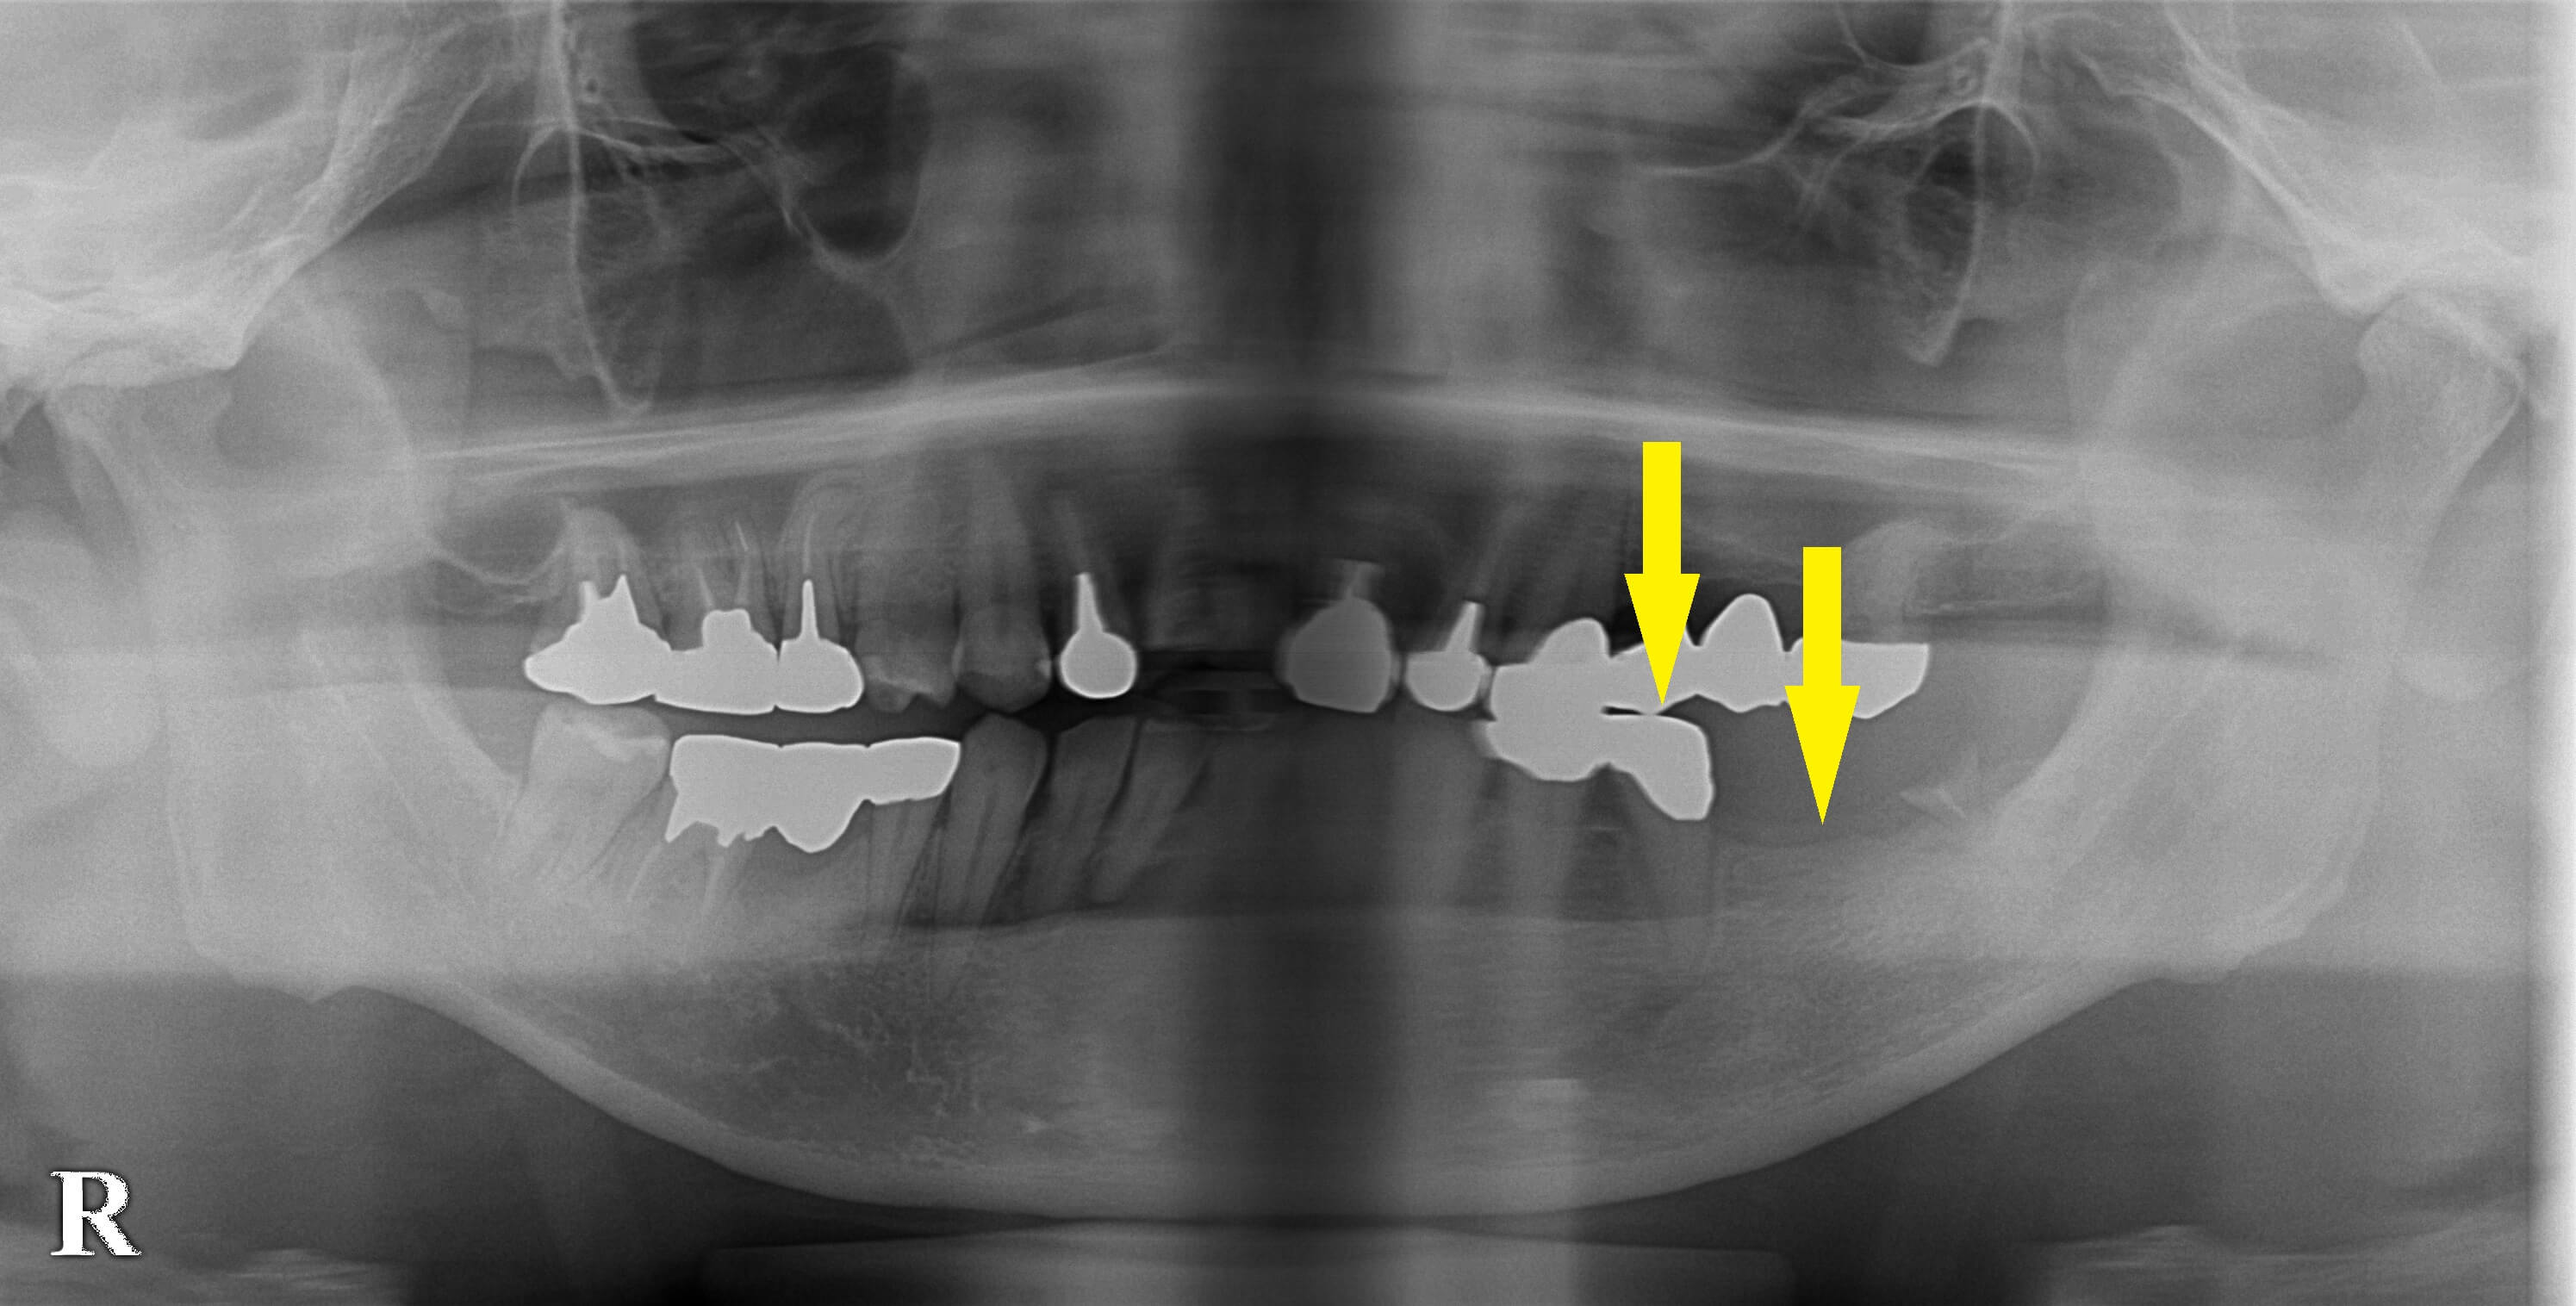

左下顎に装着されていたブリッジが外れ、後方の歯は歯根の先しか残っていない状態、ブリッジの支えになっていた前方の歯は、グラグラの状態でお出でになりました。

最近増えたパターンですが、後方の歯は抜歯、前方の歯を抜歯して即時埋入、そのすぐ後方にもう1本インプラント埋入を行いました。